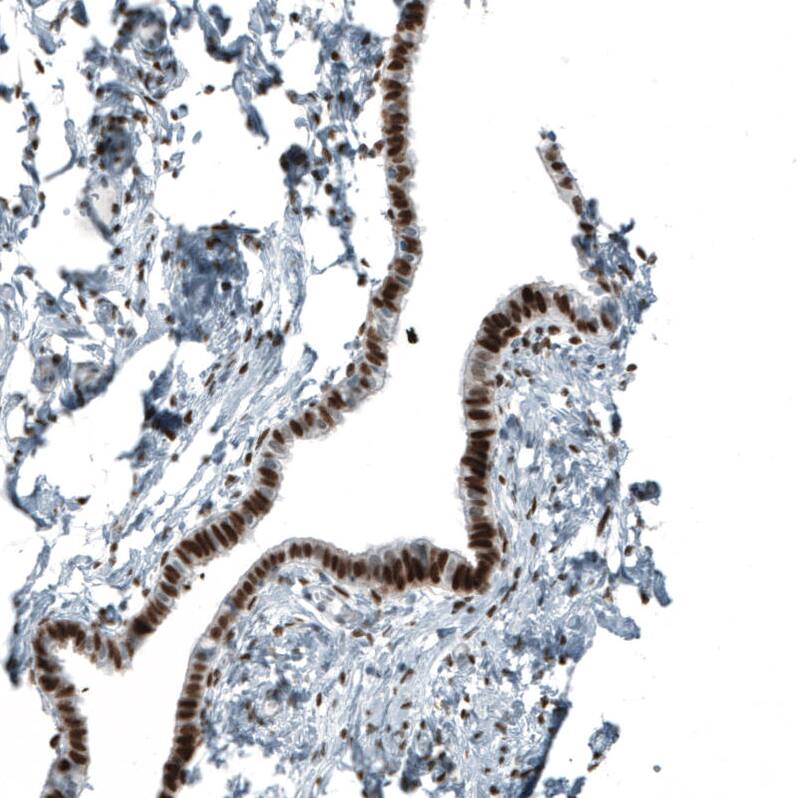

Staining of human Fallopian tube shows strong nuclear positivity in glandular cells.